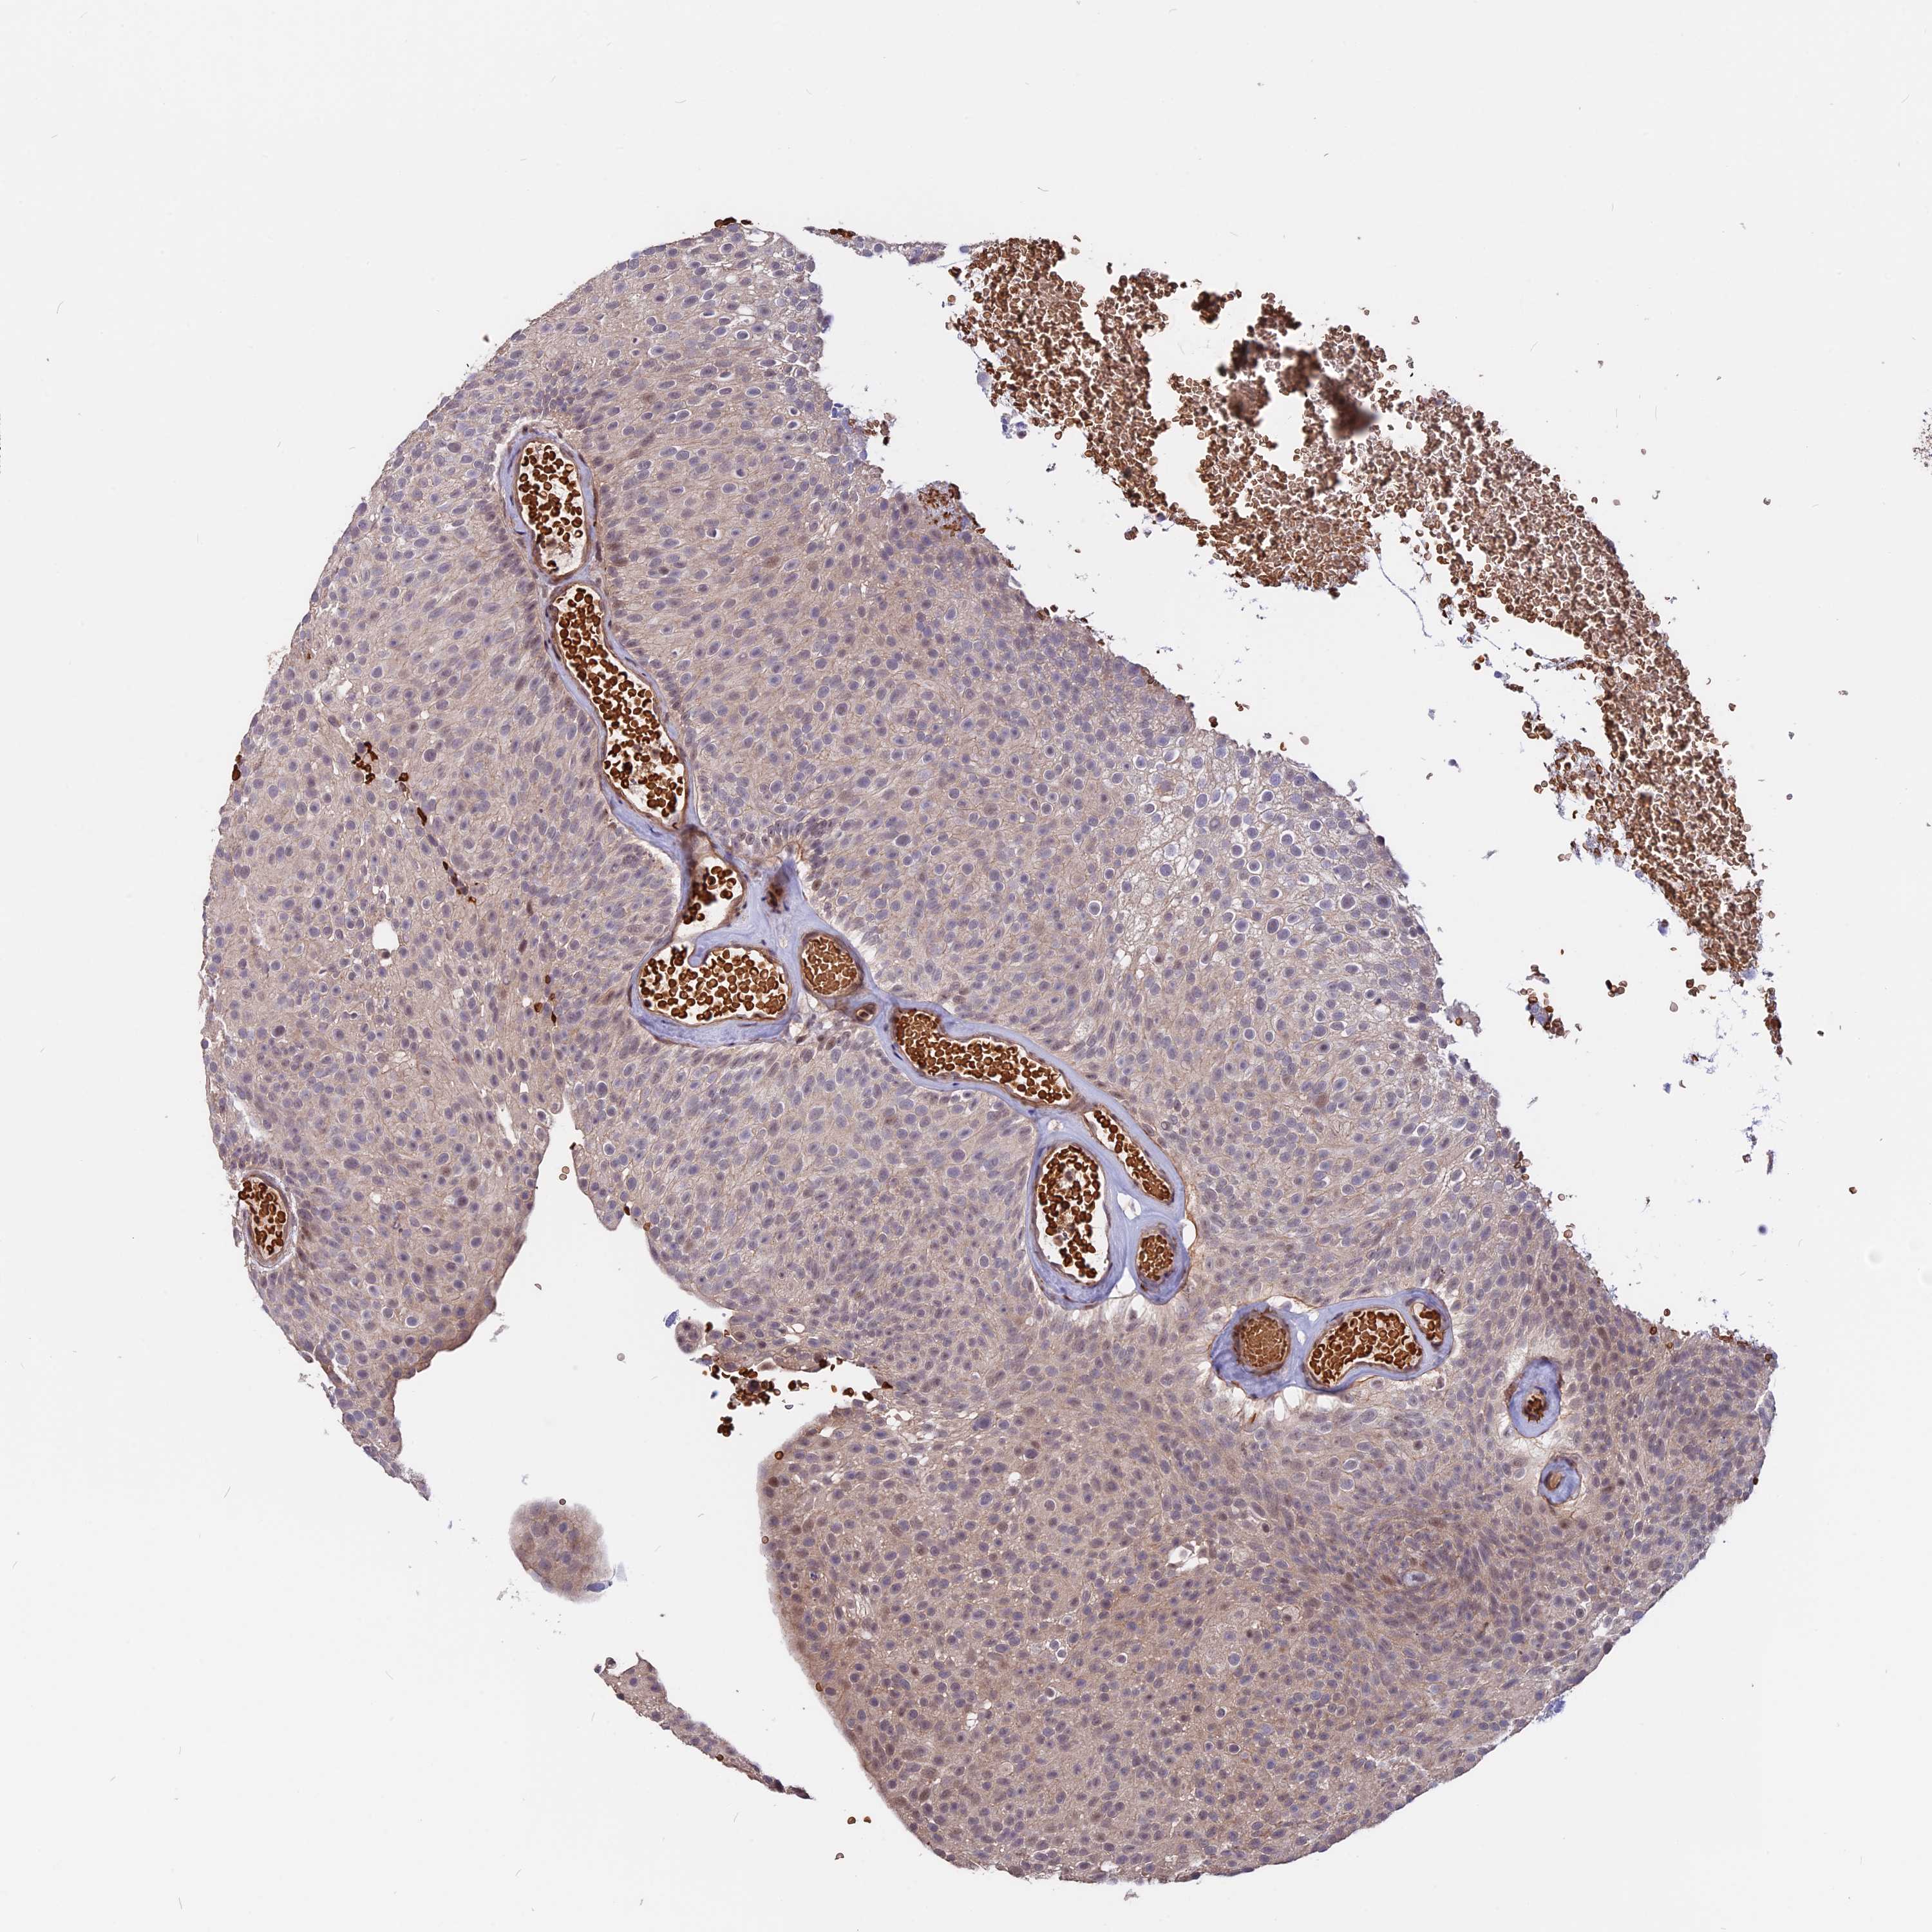

UROTHELIAL CANCER - Protein expressioni

A mouse-over function shows sample information and annotation data. Click on an image to view it in a full screen mode. Samples can be filtered based on level of antibody staining by selecting one or several of the following categories: high, medium, low and not detected. The assay and annotation is described here.

Note that samples used for immunohistochemistry by the Human Protein Atlas do not correspond to samples in the TCGA dataset.

Antibody stainingi

Antibody staining in the annotated cell types in the current human tissue is reported as not detected, low, medium, or high, based on conventional immunohistochemistry profiling in selected tissues. This score is based on the combination of the staining intensity and fraction of stained cells.

Each image is clickable and will lead to virtual microscopy that enables deeper exploration of all samples and also displays staining intensity scores, fraction scores and subcellular localization as well as patient and tissue information for each sample.

Antibody HPA039236

Staining

High

Medium

Low

Not detected

Intensity

Strong

Moderate

Weak

Negative

Quantity

>75%

75%-25%

<25%

None

Location

Nuclear

Cytoplasmic/membranous

Cytoplasmic/membranous,nuclear

Urothelial carcinoma, Low grade

Urothelial carcinoma, High grade